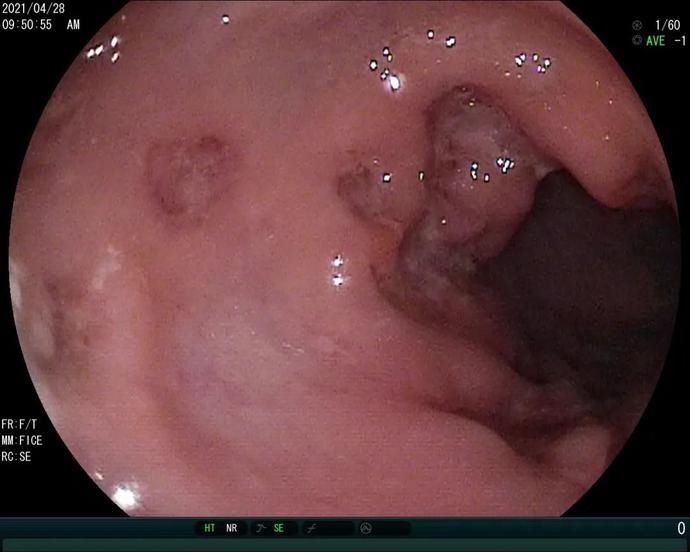

炎症性肠病(inflammatory bowel disease, IBD)是指病因不明的一组非特异性肠道炎性疾病。极早发性炎症性肠病(VEO-IBD)是指在6岁以前发病并诊断的IBD。VEO-IBD以发病年龄早、起病重、腹泻难控制、严重影响生长发育、多伴严重肛周病变、部分是基因缺陷所引起的遗传病为特点。结肠镜下表现为全结肠炎、黏膜鹅卵石样改变、深大溃疡等等。

宝宝被转到了上海瑞金医院,肖园安排宝宝做了血液、消化内镜等检查以及相关基因检测。检查结果提示:宝宝肠道内遍布大量深大溃疡、同时伴有严重的低蛋白血症,血清IL10水平明显升高,根据瑞金医院既往的研究和临床经验,临床基本上确诊为IL10RA缺陷。

原女士的宝宝肠道内的溃疡

此时如果肠镜出现全结肠累积、深大纵行溃疡就要重点考虑,如果实验室检查还发现IL10明显升高(瑞金经验>33.05 pg/ml)就可以临床确诊了。